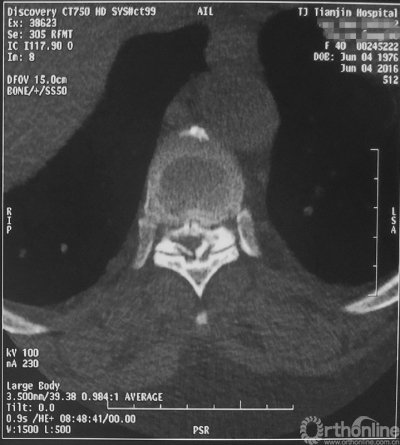

家人曾带她辗转当地治疗,因病情复杂没有得到有效的治疗,于是慕名找到天津医院脊柱外科二病区主任苗军博士诊治,当苗军主任看到躺在担架上的刘女士痛苦的表情和渴望健康的眼神,他决定收她入院为其进行手术治疗。入院检查发现,刘女士患有多节段胸椎管狭窄症,以胸8-9节段严重,椎管狭窄达80%,脊髓已严重变性。

术前CT